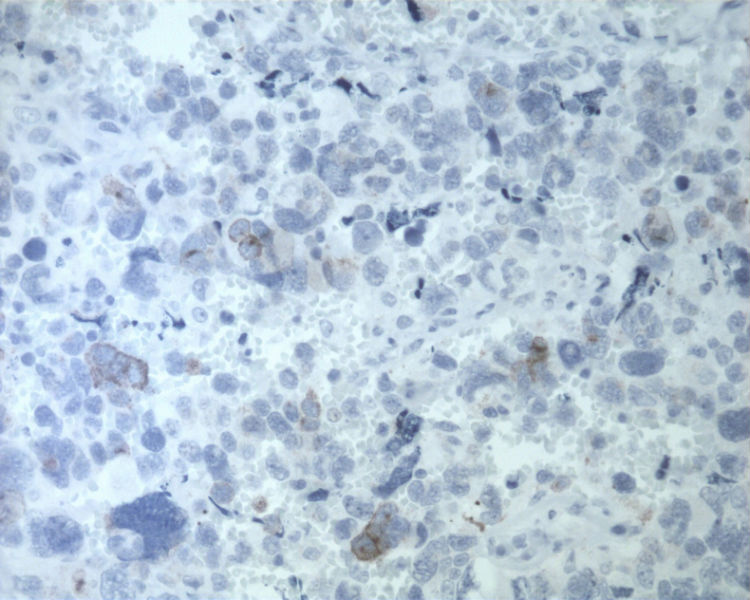

• 图1 TTF-1

名称:图1 CK

名称:图2 SYN

名称:图3 CD56

名称:图4 CGA

结合细胞腊块及免疫组化结果,诊断了淋巴结转移性的大细胞神经内分泌癌。

细胞块的细胞成分多且有成团趋势,加上IHC支持肺来源的大细胞神经内分泌癌转移至颈部淋巴结。